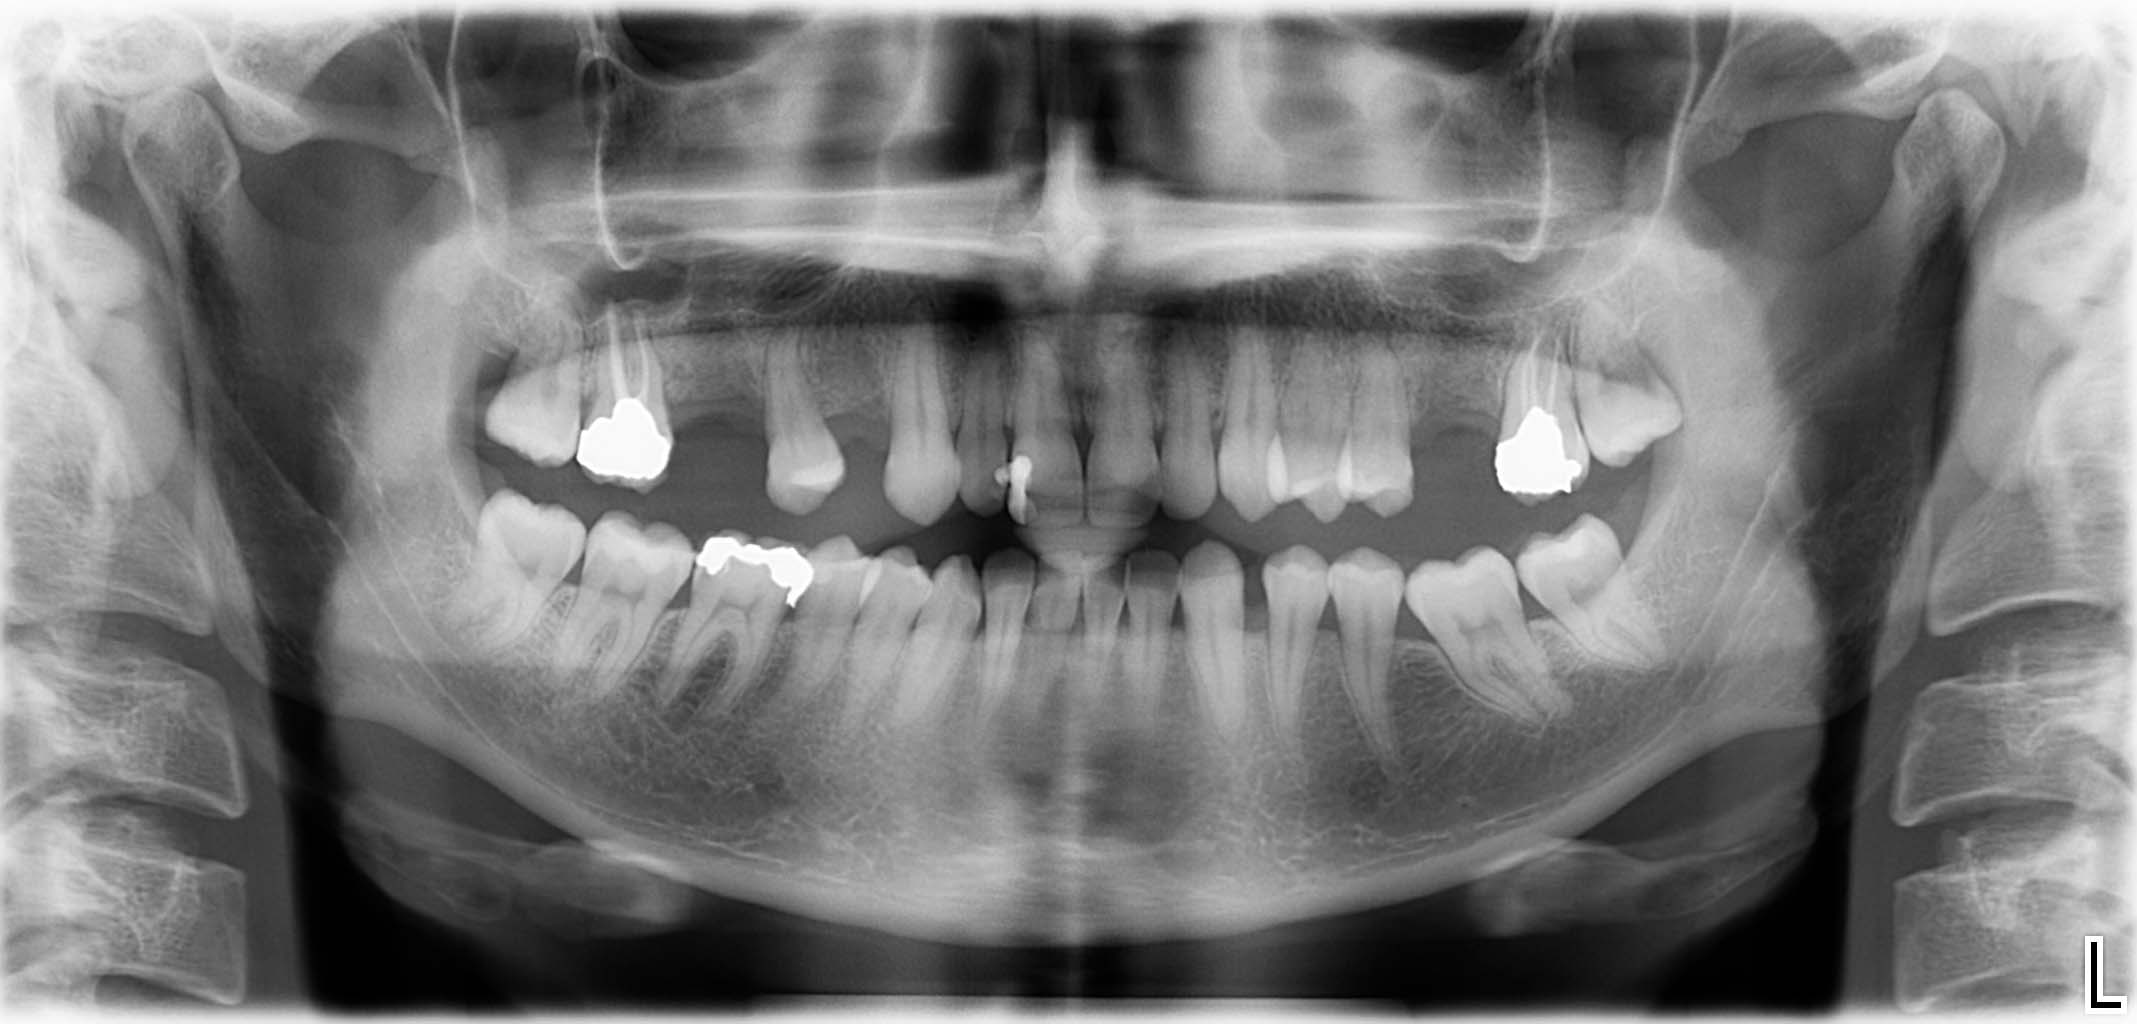

Ausgangssituation: Zahn 36 mit apikaler Beherdung, nicht erhaltungswürdig